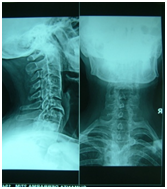

Figure 9 X-ray cervical spine: anterior and posterior longitudinal ligament calcification upto c5. C6- osteophytes formation